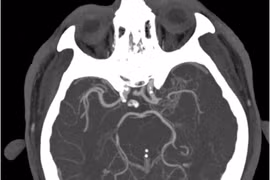

Tiêu sợi huyết, lấy huyết khối "cứu" đột quỵ não tái phát, cách gì phòng tránh?

25% đột quỵ tái phát thường gây di chứng rất nặng nề, tăng nguy cơ tàn phế, tỷ lệ tử vong cao hơn lần đầu nếu không được cấp cứu kịp thời.